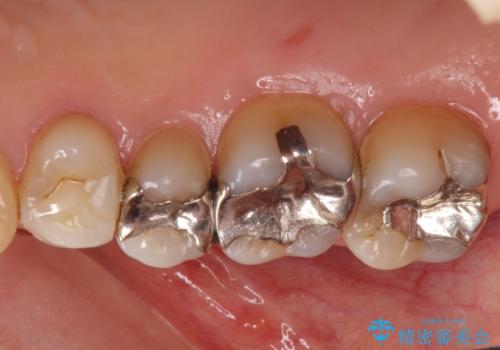

銀歯を白く 虫歯治療

- 虫歯治療を希望して来院。

保険適用の銀色のつめもののやり替えを行いました。

- 30.8万円(右上4567 emaxプレスインレー 7万円x4本)費用は治療当時の料金となります

自由診療のインレーの歯型には、シリコンを使用しています。また、処置時には8倍の拡大鏡を用いて、精密に治療しております。